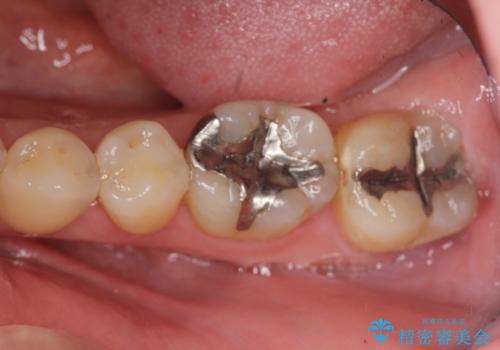

- 笑った時に見える下顎の銀歯を白くしたいと希望され来院されました。

銀歯を丁寧に外したのち、セラミックインレーによる修復を計画します。